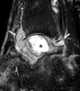

Geodes (derived from the Greek "γεώδης", meaning "Earth-like") are geological secondary formations within sedimentary and volcanic rocks. Geodes are hollow, vaguely spherical rocks, in which masses of mineral matter (which may include crystals) are secluded. [Source: Wikipedia ]